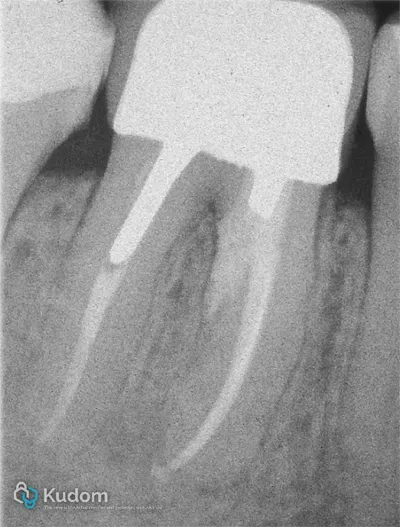

Ritrattamento di un molare inferiore con gestione di perforazione iatrogena a livello della forcazione, sotto l'imbocco radicolare.

Ritrattamento endodontico complesso di un primo molare inferiore con lesione alla forcazione e otturazione di un canale laterale con successivo build-up per overlay a ricopertura cuspidale.